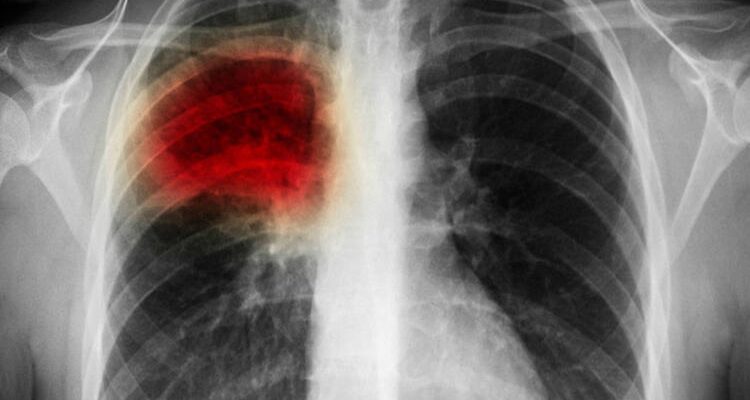

Akciğer kanaması, akciğerlerinde birinde veya daha fazla damarda ortaya çıkan tıkanmalar sonucunda akciğer kanaması tedavisi uygulanması gerekiyor.

Akciğerlerde oluşan tıkanıklıktan sonra kan akışında düzensizlik oluşur ve engellenmiş olur. Bu sorun karşısında hayatın tehlikede olduğunu ve ciddi sorunları beraberinde getireceği anlamına gelir.

Her şeyden önce hastaların tedavi edilebilir olması için mutlaka uzman hekimlerimiz tarafından ön muayenenin gerçekleşmesi gerekir. Daha sonra herhangi bir şüphe ile karşı karşıya kalındığında, kesin tanı koyabilmek için bazı testlere ihtiyaç duyulur.

Yapılacak olan testlerden önce pıhtı oluşumunu önlemek için enjeksiyon yardımı ile ilaç yapılır. Burada Antikoagülan denilen ilaç ile pıhtının oluşumu ve büyümesi önlenmiş olur. Elde edilen sonuçlar doğrultusunda hastanın durumu ele alınır ve akciğer kanaması tedavisi, için gerekli olan çalışmalar başlatılmış olur.